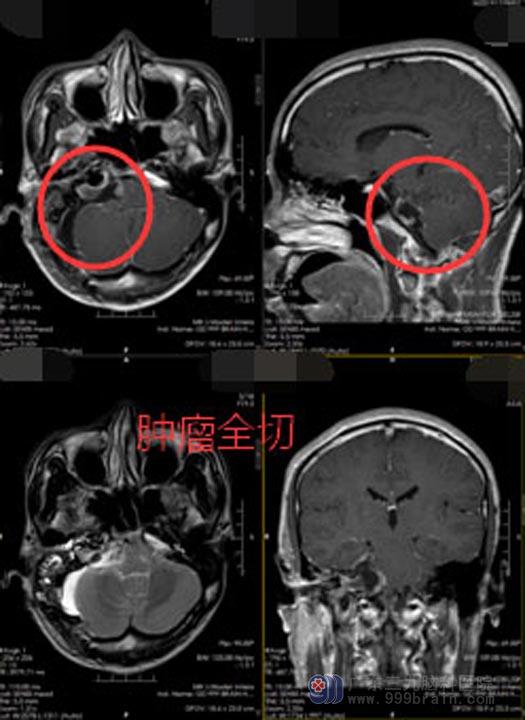

住院期间,龙先生认识了很多病友,看到他们都能开开心心地出院,龙先生也增强了自己战胜疾病的信心。由医院副院长、神经外五科主任主刀在全麻下行“右侧桥小脑角区听神经鞘瘤”切除术,手术非常顺利,肿瘤切除干净。术后,龙先生面部疼痛症状消失,听力也有改善,没有出现手术并发症。

▲手术后